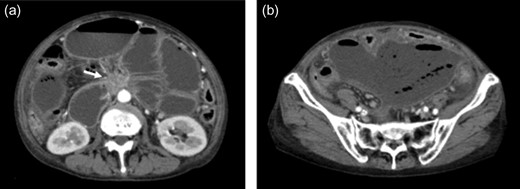

Contrast-enhanced abdominal computed tomography (CT) revealed a 48 × 28 mm mass in the pancreatic head that had invaded the whole circumference of the SMA. The SMA was occluded by the invasion of pancreatic cancer, and almost all of the small intestine was dilated with a very thin wall that was not enhanced (Figs 1 and 2). We diagnosed the patient with peritonitis and extensive necrosis of the small intestine due to SMA occlusion by the invasion of pancreatic cancer.

(a) Contrast-enhanced CT revealed a 48 × 28 mm mass in the pancreatic head (white arrow). Extensive intestine became ileus. (b) In the lower abdomen, the intestine showed no contrast effect, suggesting intestinal necrosis.